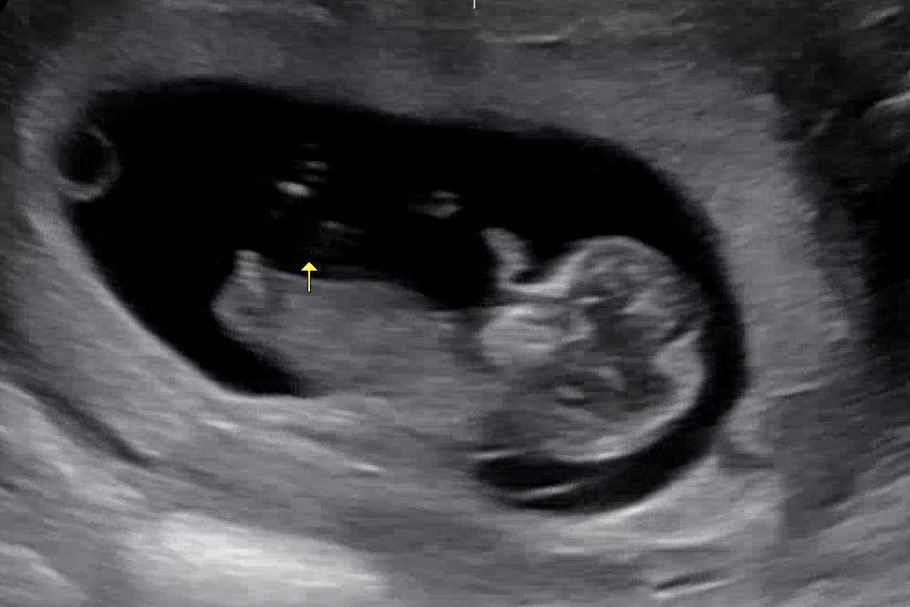

11주차 좀 이르지만 각도법 봐주세요🫶

안녕하세요!! 원래대로라면 10주5일차지만 금방 커서 예정일이 당겨졌어요ㅎㅎ 그래거 지금은 11주2일차! 조금 많이 이르지만 궁금한건 어쩔수없네용😅 각도법 아시는 고수님들!! 마구마구 부탁드립니다🫶